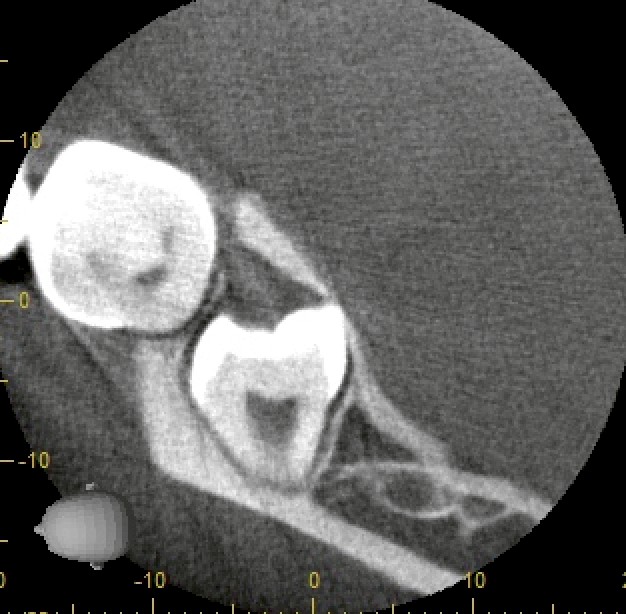

CT撮影で三次元的に評価

そこでCT撮影を実施。

結果は明確でした。

歯根が頬側、歯冠が舌側。

つまり、頬舌的に倒れ込んでいる埋伏智歯。

この情報があるかないかで、術式戦略は大きく変わります。

このタイプの抜歯で起こりやすい問題は:

・最終抜去時に歯冠が舌側骨に引っかかる

・無理な挺出で歯質破折

・舌側軟組織損傷リスク

今回も最終段階で歯冠が明らかにロックされることが予測できたため、

あらかじめ歯冠分割を行い、撤去方向をコントロール。

無理な力をかけず、安全に摘出しました。